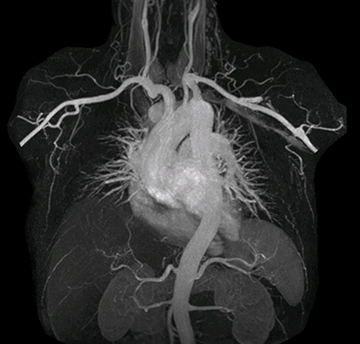

“In MRA, the capacity to acquire a sequence in a single breathhold provides images that are motion-free and high in contrast and detail, advantages that aid in diagnosis,” he says. “With Compressed SENSE, we can reduce the time for the single breath-hold to just 2-3 seconds. Before Ingenia Ambition and Compressed SENSE, the breath-hold requirement was about 8 to 9 seconds, which was too long for some patients.”

“In our peripheral MRA run-off studies with Ambition we realize key benefits, including outstanding image quality and significantly reduced breath-hold and scan times, which not only benefit the patient, but also provide the opportunity to add sequences that could aid in diagnosis,” Dr. Peña says.

“Before we had Ingenia Ambition, our CE-MRA run-off studies would first acquire a dynamic pre-contrast scan with 20-25-second breath-holds, then inject the contrast, do another acquisition and then subtract the two,” says Avila. “Now, mDIXON XD allows us to complete the study in just one single pass – without need for a pre-exam – which eliminates subtraction artifacts and almost halves the scan time. In addition, mDIXON provides much better background suppression, which really improves vesselto-background contrast. And, thanks to Compressed SENSE, the single breath-hold is not long and we improve image resolution.”

The subtractionless peripheral MR angiography shows improved vessel-to-background contrast and high resolution. Ingenia Ambition 1.5T.